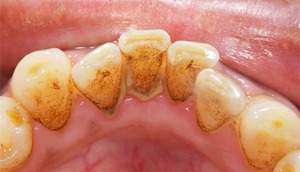

歯石除去

治療前

治療後

| 年齢 | 25歳・男性 |

| 主訴 | 歯石をとりたい・検診 |

| 治療内容 | 各種検査・歯石除去 |

| 治療期間 | 60分 |

| 費用 | 初診料3,000〜4,000円前後 +歯石除去約1,000円 |

| リスク・副作用 | ・処置後に歯がしみることがあります。 ・歯と歯の間に隙間ができるので、息が漏れ発音しにくいと感じることがあります。 ・歯ぐきの炎症が軽減すると歯ぐきが引き締まり、歯が長く見えることがあります。 |

| 担当者所見 | 前歯の裏側にすぐに歯石が溜まってしまいザラザラして気になるとご相談いただいたので適切な歯ブラシの当て方とフロスの通し方をお伝えさせて頂きました。 |